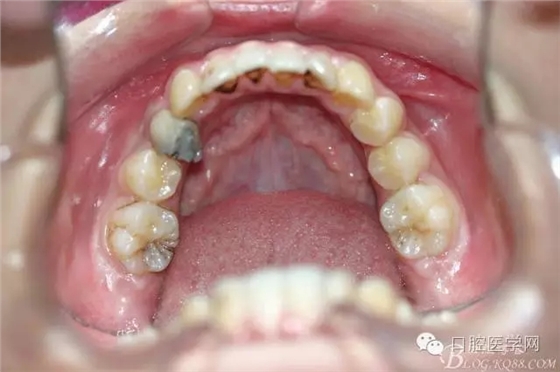

正畸查:替牙合。第一恒磨牙中性合。上牙弓尖圓型下牙弓方圓型。前牙覆合3度覆蓋7.5mm。下前牙咬到上舌側(cè)牙齦。上頜擁擠4.0mm,下頜擁擠

3.0mm。上頜稍前突下頜后縮,上下唇前突,上前牙覆蓋下唇,下唇外翻。面下三分之一過短,頦唇溝明顯,開唇露齒,頦饜窩明顯。顳下頜關(guān)節(jié)開閉口無彈響,無壓痛,開口型開口度正常。

正畸前照片: